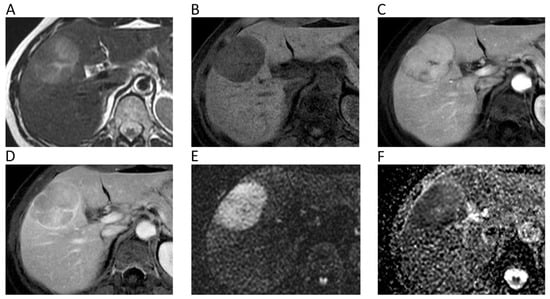

6. Hepatobiliary

| Hepatobiliary | Miller, F.H.; et al. J. Magn. Reson. Imaging 2010 [32] | Retrospective; 542 focal liver lesions in 382 patients; 1.5T MRI. | Mean ADC (10−3 mm2/s) of hemangiomas = 2.26, FNH = 1.79, adenomas = 1.49, abscesses = 1.97, HCC = 1.53, and metastases = 1.50. Mean ADC of benign lesions = 2.50, malignant lesions = 1.52. Overlap reported between solid benign and malignant lesions. |